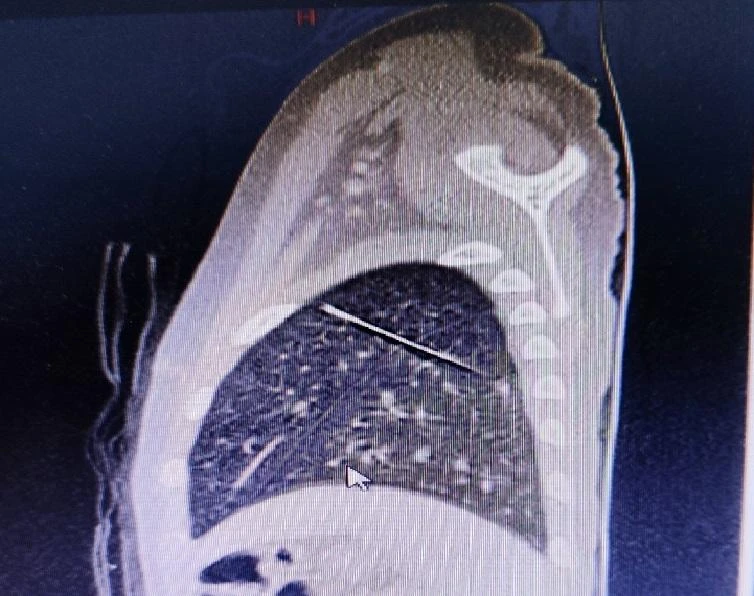

Hình ảnh dị vật là chiếc kim may nằm sâu trong nhu mô phổi trái bé T. Ảnh: BV Nhi đồng2. |

Tại đây, bé được thăm khám và tiếp tục được chụp CT scan, ghi nhận dị vật hình dạng kim may áo quần nằm trong nhu mô phổi trái, xuyên từ thùy dưới lên thùy trên.